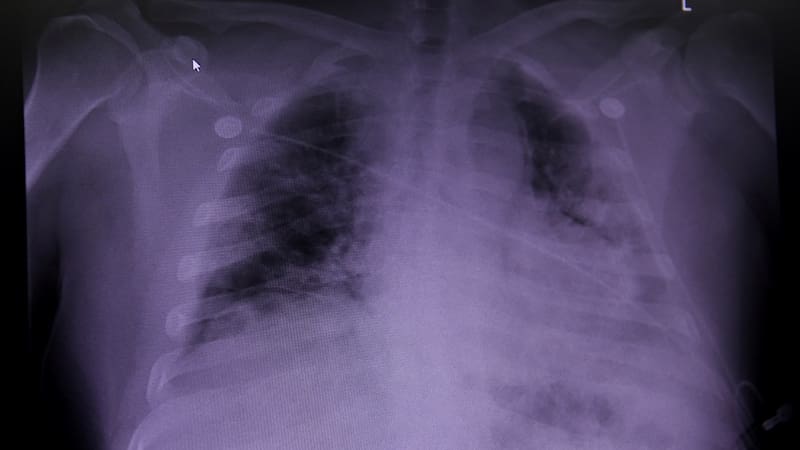

Caos en los pulmones

El conjunto de hallazgos más extenso fue el de los pulmones. Los científicos quedaron asombrados por el alcance de los cambios en los programas genéticos que encontraron allí. “El virus causa estragos en los pulmones y lo vemos en las células”, dijo Regev.

Una de las principales causas de daño pulmonar en Covid-19 es la destrucción de las células AT1, que permiten la respiración y la transferencia de gases. Los científicos descubrieron que cuando las células AT1 murieron, las células pulmonares relacionadas llamadas AT2 intentaron convertirse en células AT1 a través de un proceso llamado transdiferenciación. Pero este intento se detuvo a mitad de camino, dejando a las células en un estado intermedio que a menudo se observa en pacientes con otras enfermedades pulmonares como la fibrosis pulmonar.

En un último intento de autorreparación, los pulmones intentaron convertir las células de más arriba en las vías respiratorias, conocidas como células progenitoras intrapulmonares de tipo basal, en células AT1. Este intento de transdiferenciación solo se había visto previamente en modelos de ratón.

Los hallazgos sugieren que la insuficiencia pulmonar en los pacientes fue causada por la incapacidad de las células pulmonares para superar el daño causado por el virus cuando las células intentaron regenerarse.